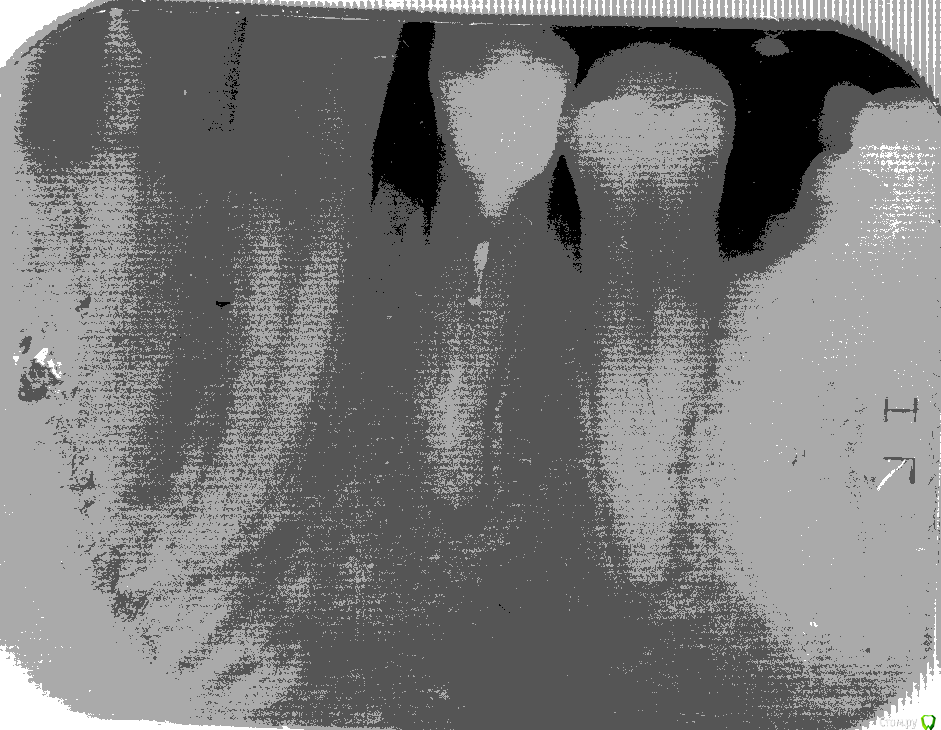

Игорь4444 Опубликовано 8 августа, 2019 Поделиться Опубликовано 8 августа, 2019 (изменено) Здравствуйте. Начну чуть издалека, что бы стало понятно.4. Заболел пятый слева внизу зуб. Удалили. Заодно выломали пломбу на шестом зубе слева внизу.Тут, я предполагаю, произошло занесение инфекции.2. Потому что вторым пунктом была чистка у другого хирурга лунки пятого зуба слева внизу. По ощущениям до челюсти,.3. Заболел шестой зуб слева внизу. Высверлили два канала, дали стечь гною. Зуб полностью прошёл, вплоть до того, что когда чистили каналы, ощущались только уколы иголкой и текла только кровью. Поставили лекарство и временную пломбу.4. Постепенно началась дикая боль. "Коктель" из найза, кеторола и нимесила не помогал.5. Обратился утром следующего дня в стоматологию. Делать зуб отказались, посоветовали пить нимесил и цитрофан ст.6. Пришлось идти к другому стоматологу. Результат: рассверленный канал зуба шестого слева снизу, вскрытая десна с дренажём.7. Пока шестой зуб и десна заживали до приемлемого состояния, сделали четвёртый справа снизу зуб. Сделали хорошо, но, когда прошла местная анестезия, зуб начал болеть. На стыке зуба и десны образуется кольцо белой, густой слизи. Похоже гной. Нимесил помогает.Дополнительный симптом: запах гноя изо рта.Даю ссылку на 3д снимок нижней челюсти после второй чистки шестого слева зуба до установки пломбы в четвёртый справа зуб.https://yadi.sk/d/8M6hcnKM9MW5VgИ сегодняшний снимок четвёртого справа снизу зуба приложил. Скан копия снимка. Две фотографии снимка.Сам предполагаю, что во рту у меня какая то инфекция, типа стафилококка, которая не позволяет пломбировать зубы.Прошу помощи, потому что местные врачи не справляются. Изменено 8 августа, 2019 пользователем Игорь4444 Ссылка на комментарий

Игорь4444 Опубликовано 9 августа, 2019 Автор Поделиться Опубликовано 9 августа, 2019 Я благодарю всех откинувшихся!Прошу прощение за молчание. Приходил в себя после лечения.По совету Red_butler начал лечение четвёртого справа снизу зуба.Вскрыли канал.Как выяснилось, когда зуб пломбировали, то делали только рестоврацию верхней части. Канал был запломбирован предыдущим врачём. Предположительно канал был запломбирован негерметично, поэтому возник воспалительный процесс под зубом, который обострился при герметизации зуба.Теперь жду три дня. Через три дня будут решать: ставить сразу постоянную пломбу или лекарство.По совету Сирены узнал где есть пародонтолог. Завтра буду договариваться с ним о лечении.По результатам отпишусь.Ещё раз благодарю! 2 Ссылка на комментарий